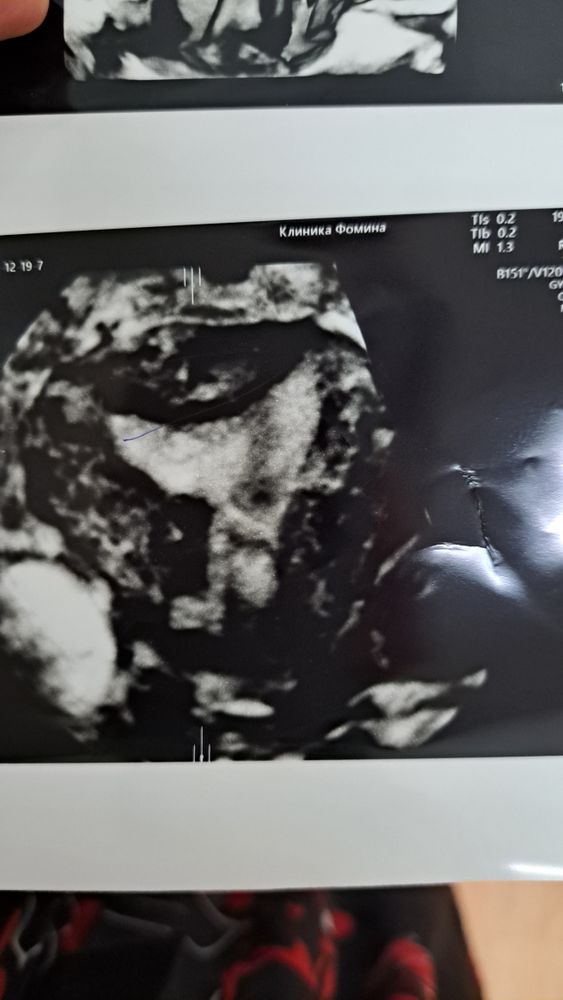

Арина, вот кстати фото 3д узи. Изображение Изображение Изображение Изображение Изображение в этом треугольнике серенькое - это эндометрий. и он однородный типа. справа кальценат. а вот блиде к шейке какая то фигня